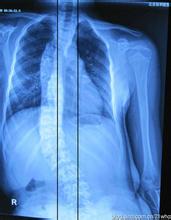

在强直性脊柱炎患者当中,还有部分患者倘若治疗不及时,病情就会容易并发肺部疾病,这一后果主要出现在晚期,累及肋骨的情况已经相当严重,肺部功能已经受到了严重的影响,导致患者有咳嗽、咳痰、呼吸困难等症状。检查时会发现患者的双侧肺不张,肺功能表现为下降。>>>强直性脊柱炎会导致瘫痪吗?点击免费咨询专家